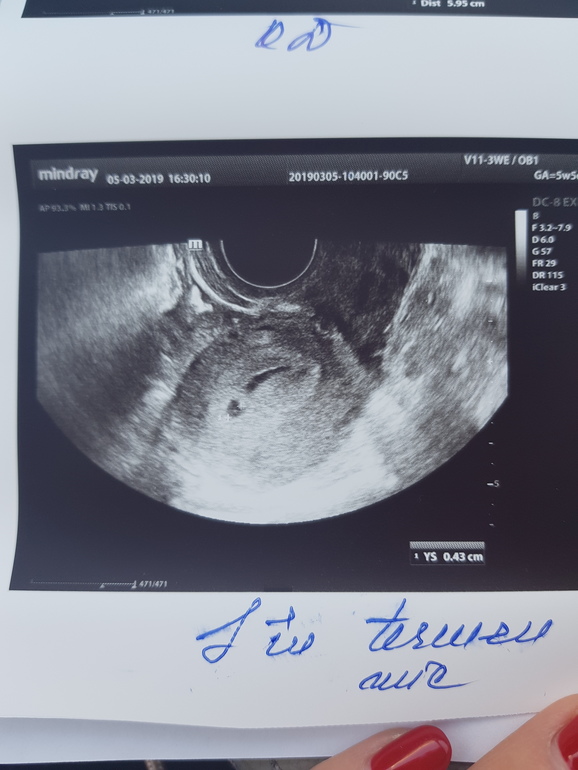

Вчера была на узи, чтобы исключить внематочную. Нашли плодное яйцо 4,3 мм и большую гематому рядом 19,1 на 5,6 мм. И еще кисту желтого тела 5 см.

Посмотрите,пожалуйста узи,кто разбирается. Поначиталась гематома это отслойка, но у меня она отдельно от яйца.. не похоже на отслойку. С дочкой все было идеально, ни разу никаких проблем не было..

Вот фото узи

Гематома отдельно